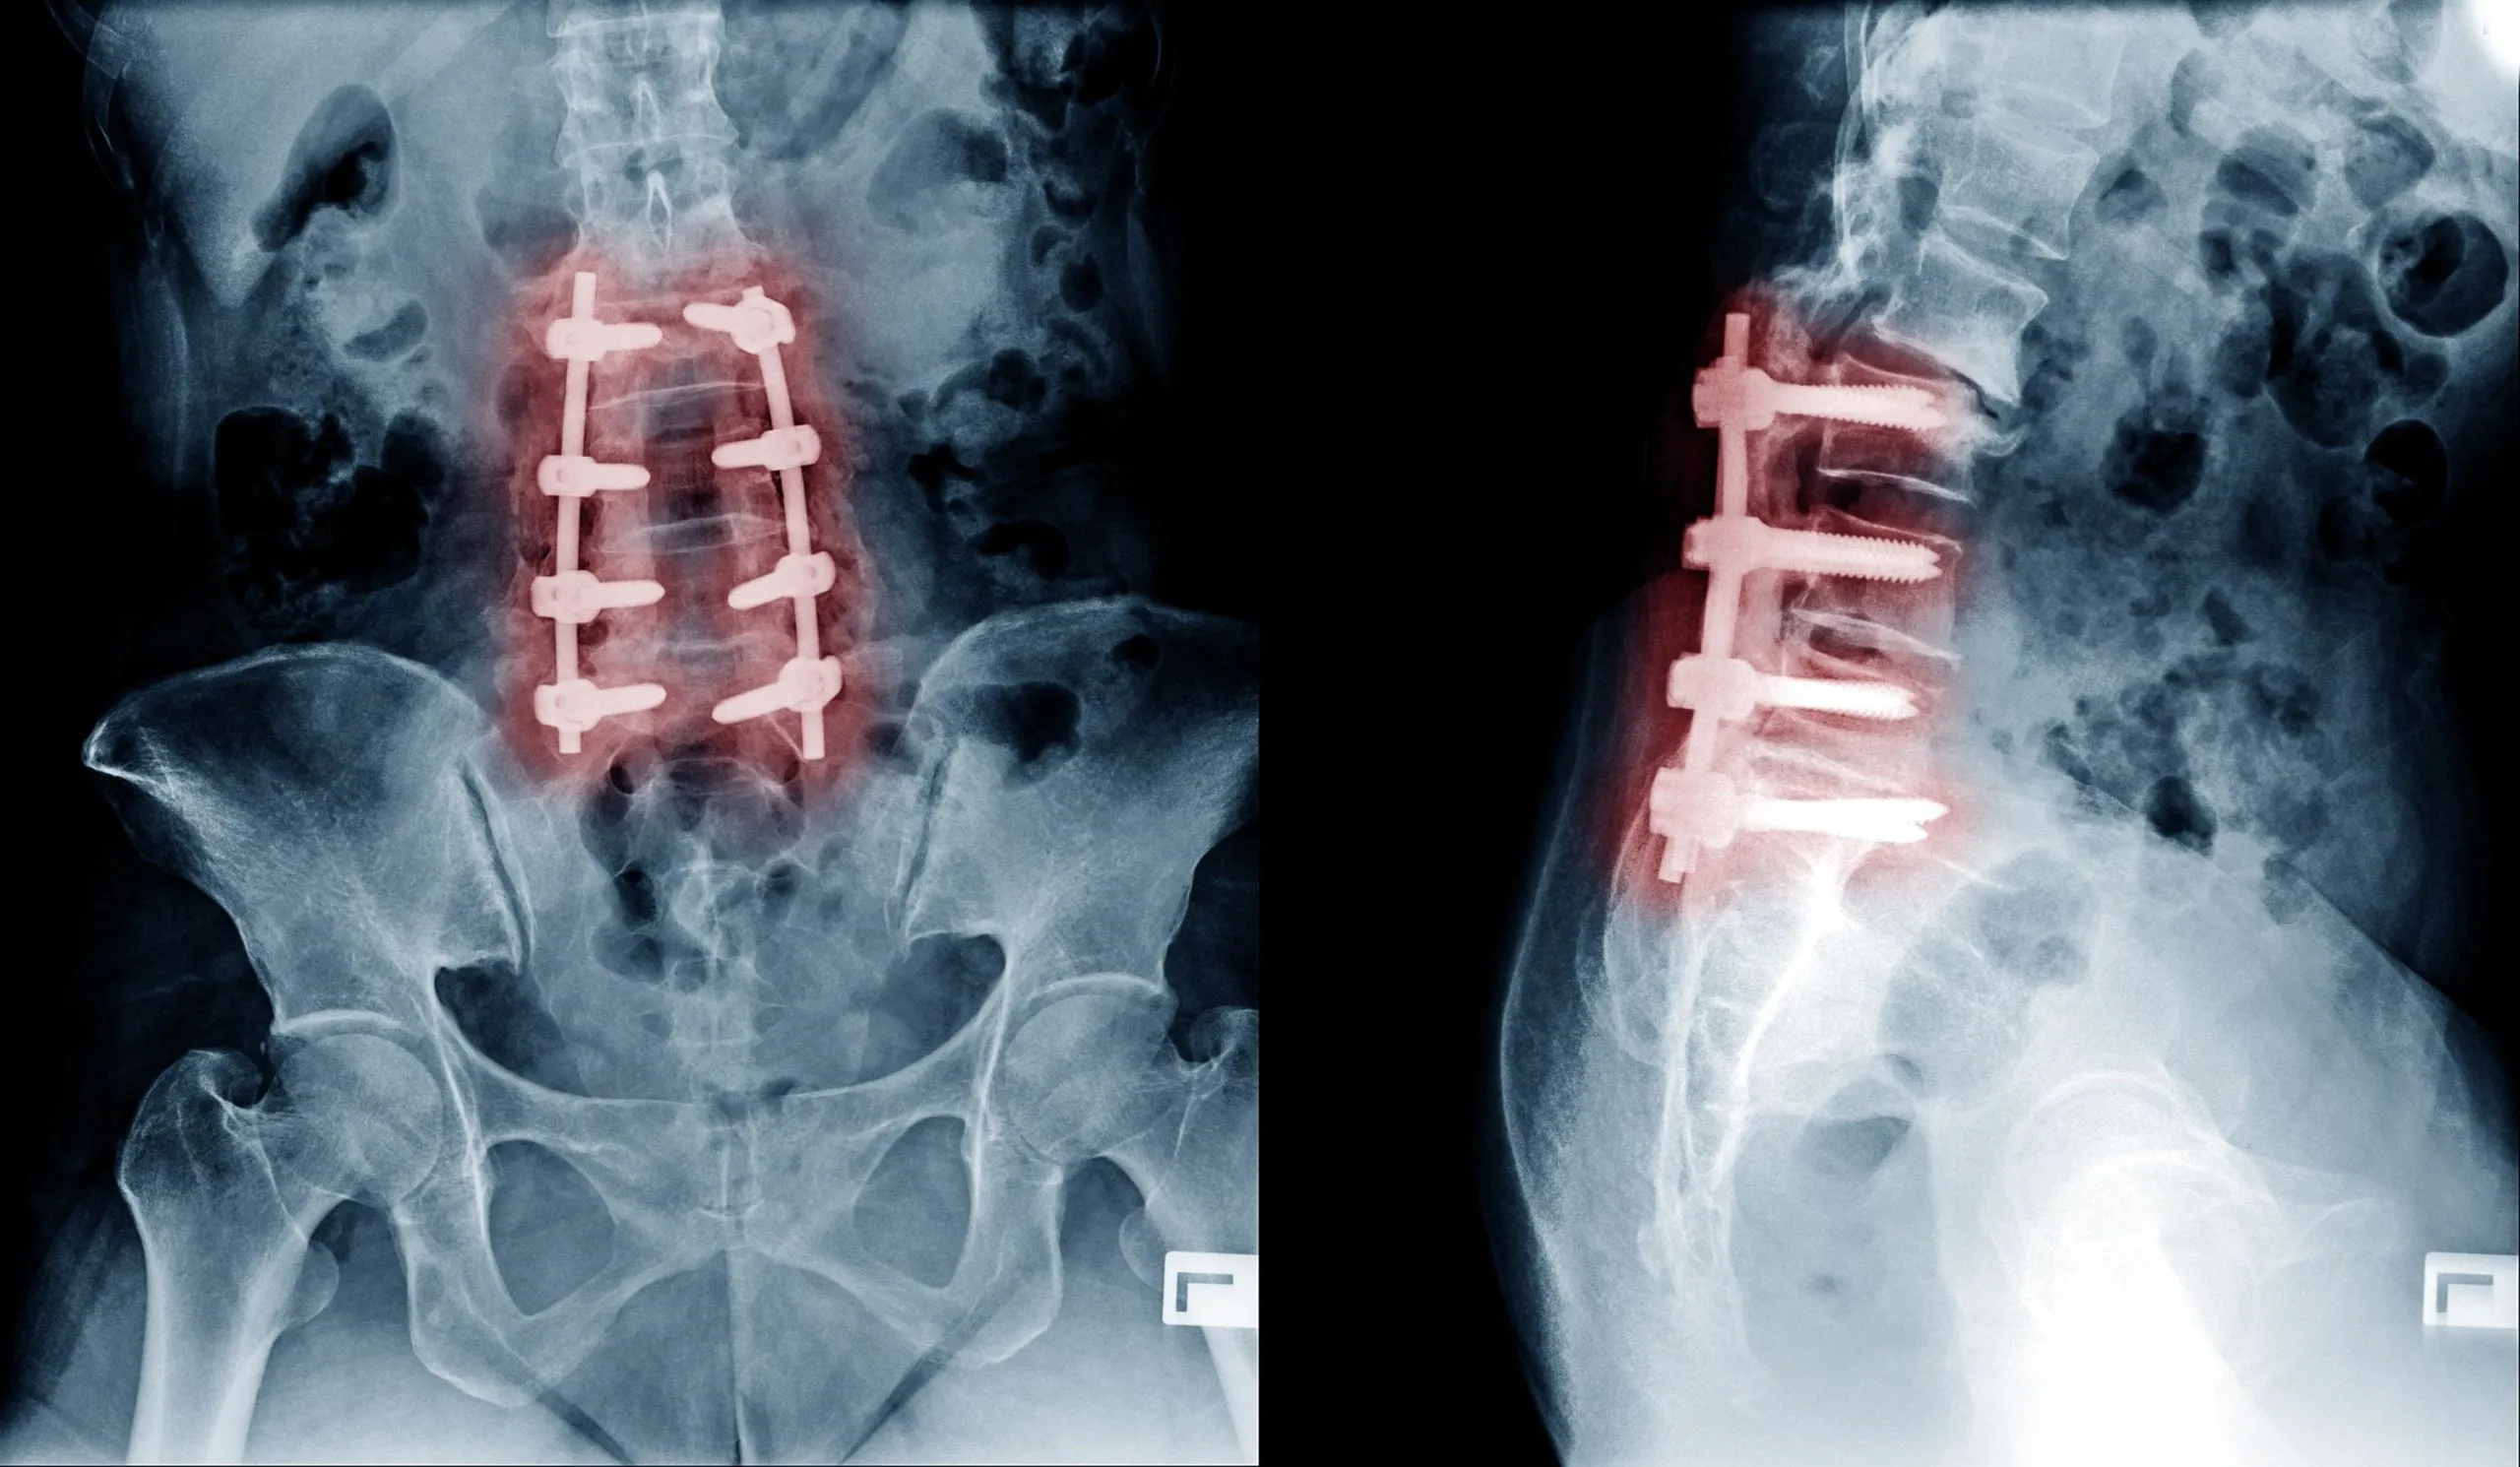

The marketing brochure version of spinal fusion is that it eliminates pain by stopping motion at a damaged segment. The published outcome data is more sobering.

A widely cited study in the European Spine Journal found that the minimal clinically important difference for back pain was achieved in only about 50% of patients after lumbar fusion. 10 That is the same statistical outcome as a coin flip, for a procedure that involves cutting bone, implanting hardware, and permanently locking spinal segments.

Beyond the immediate failure rate, fusion creates a cascade of downstream problems:

Adjacent segment disease. When two vertebrae are fused, the segments above and below are forced to absorb the motion the fused level no longer provides. Over years, those adjacent levels degenerate at an accelerated rate. A meta-analysis of 19 studies covering nearly 3,000 patients found an overall adjacent segment disease rate of 18.6% after posterior lumbar fusion. 3 A 2025 systematic review reported adjacent segment degeneration in 36% and clinically symptomatic adjacent segment disease in 11% of fusion patients within two to seven years of surgery. 11 Many of these patients return to the operating room for a second fusion, then a third.

Surgical complications. Complications of spinal fusion occur in up to 18% of patients, ranging from infection and blood clots to stroke, pneumonia, heart and lung problems, and death. 1

Hardware failure. Screws loosen, rods break, cages migrate. Each hardware problem typically requires another operation.

Pseudarthrosis. The bone graft fails to fuse in a meaningful percentage of cases, leaving the patient with hardware, motion at a level that was supposed to be locked, and pain.